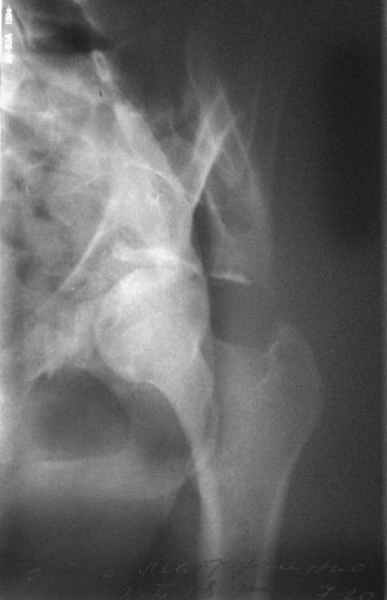

Посылаю схемы и 3D реконструкцию подобного повреждения. Называется он полным высоким двухколонным переломом вертлужной впадины, а "переломы крыла и тела подвздошной кости" входят в это понятие.

Вариантов остеосинтеза много (можно и не оперировть, т.к. конгруентность при таких переломах как правило сохраняется)

1 закрытая репозиция аппаратом + фиксация через проколы винтами

2 закрытая репозиция передней колонны + открытая задней колонны из задне-неружного доступа

3 открытая репозиция передней колонны из подвздошнго доступа + открытая задней колонны из задне-наружного доступа

4 открытая репозиция из илиоингвинального доступа

5 открытая репозиция из Y образного доступа

Я бы ориентировался на Y образный доступ

или из двух если есть сомнения в целостности задних отделов крыла.

прикладываю схему доступа и случай.

Одним задне наружным переднюю колонну не достать, а илио-ингвинальный более сложный не позволяет контролировать суставную поверхность и трудно управлять задней колонной.